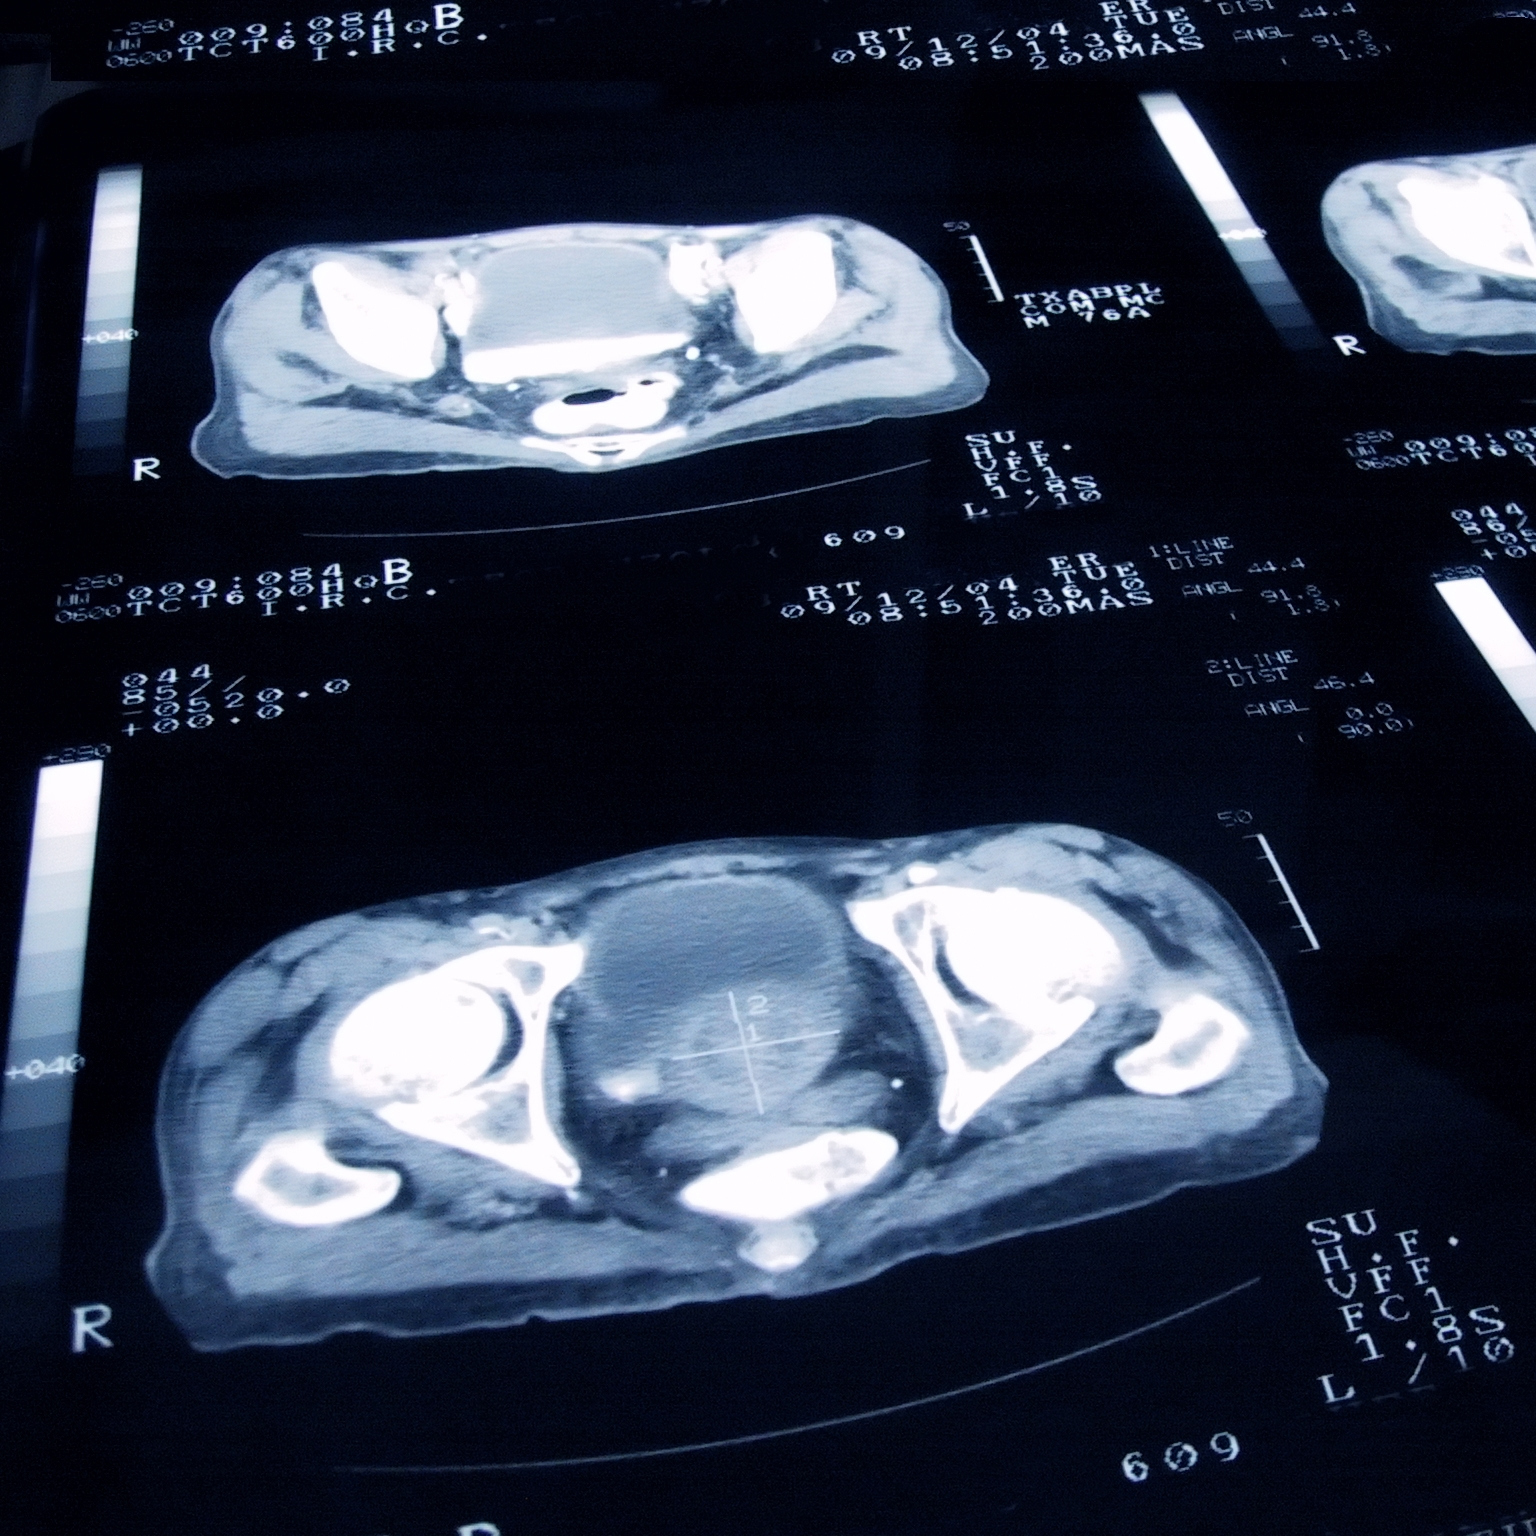

前列腺癌通常可以通过手术或放疗治愈。但大约三分之一被诊断患有前列腺癌的男性患有晚期前列腺癌,这种治疗并不总是有效,或者已经扩散到前列腺以外(这意味着癌症已经扩散)转移性).对于这样的男性,激素疗法可以减缓癌症的进展。你会问,怎么做到的?让我们来看看男性性激素(或雄激素)在前列腺癌中的作用,以及抗雄激素(抗雄激素)这类激素治疗药物是如何帮助与前列腺癌抗争的男性延长寿命的。

阉割指的是任何阻止睾丸产生睾丸激素的干预措施,无论是手术还是药物,在过去的75年里,它一直是治疗晚期前列腺癌的主要手段。虽然有些男性会选择手术切除睾丸,但最常见的方法是药物治疗。这两种方法同样有效。最后,阉割不是一种治疗方法。洛杉矶加州大学洛杉矶分校泌尿肿瘤研究所前列腺癌项目医学主任、医学肿瘤学家Matthew Rettig博士说:“几乎所有晚期前列腺癌患者都对这种治疗有反应,但他们最终都会对阉割产生耐药性。”输入:抗雄激素。